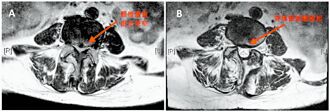

糖尿病患者比一般人更容易脊椎退化,接受脊椎手术后,伤口感染风险也更大。一名52岁李先生,罹患糖尿病多年,长期久坐导致第4、5腰椎严重退化狭窄,下背痛及腿部麻木,甚至无法正常行走,接受新式超音波骨刀内视镜手术后,不仅顺利避免感染,恢復期也比预期短、术后疼痛明显减轻,重拾健康生活。

一名52岁李姓工程师罹患糖尿病多年,长期久坐导致第4、5腰椎严重退化狭窄,下背痛及腿部麻木,甚至无法正常行走。李先生原本担心脊椎手术有高感染风险,今年在基隆长庚接受新式「超音波骨刀内视镜手术」,不仅顺利避免感染,恢復期也比预期短、术后疼痛明显减轻,重拾健康生活。